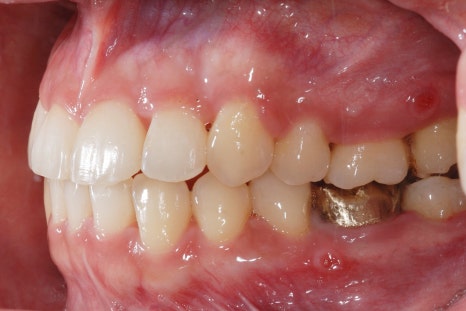

<교정치료 전후 사진>

치료기간: 23.01.18 - 24.6.04 (약 1년 6개월)

진행한 치료: 돌출, 중심선 개선

*치료 전후 사진은 환자의 동의하에 게재하였으며, 동일한 환경과 조건에서 촬영된 전후 사진입니다.